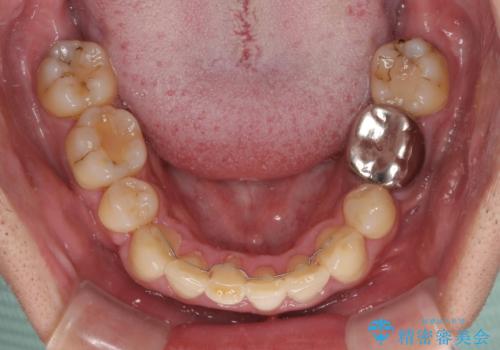

第二小臼歯抜歯の矯正治療は、治療期間が長引くことが多いですが、動きが非常に良く、予定の治療期間で終えることができました。

上下の正中も思っていた以上に良い位置に改善されました。